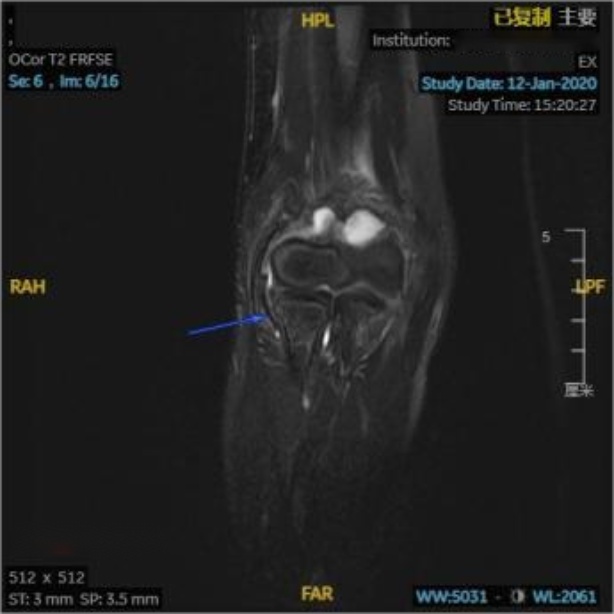

在对照MRI影像横断位,可见环绕桡骨头的环状韧带连续性完整,与桡骨头间充满高信号韧带下积液(见图3(a)图3(b)蓝箭头);在对照MRI影像冠状位(见图3(c)蓝箭头),可见关节腔内充满高信号的关节积液,积液内可见一明显低信号带状影,未见低信号影嵌入关节内,提示环状韧带连续性良好未嵌入肱桡关节内;在对照MRI影像矢状位(见图3(d)图3(e)蓝箭头),可见肘关节内有高信号的关节积液,关节间隙旁可见一低信号带状影,形状完整,连续性良好,并未嵌入关节间隙内。

放射学复位后,即复位后X片提示桡骨干轴线无明显偏离肱骨小头骨化中心,但患儿仍存在肘关节活动受限,此种情况即视为解剖学复位失败,其MRI影像表现为:横断位可见环状韧带局部变薄,与桡骨头之间可见高信号积液,韧带局部不再环绕桡骨头,与桡骨头交界处模糊(见图4(a)红箭头);冠状位可见环状韧带局部变薄,疑似连续性中断,脱套的环状韧带呈低信号,其上半部分卡压于肱桡关节间隙中,关节间隙内见带状液性高信号,关节周围可见软组织肿胀(见图4(b)红箭头);矢状位可更直观清晰的看到在关节间隙中的高信号关节积液衬托下,嵌入肱桡关节内的低信号环状韧带;除此之外也可见尺骨鹰嘴近端骨皮质信号不连续,断端间对位对线良好,整个左肘部周围肌肉均有广泛肿胀(见图4(c)红箭头)。